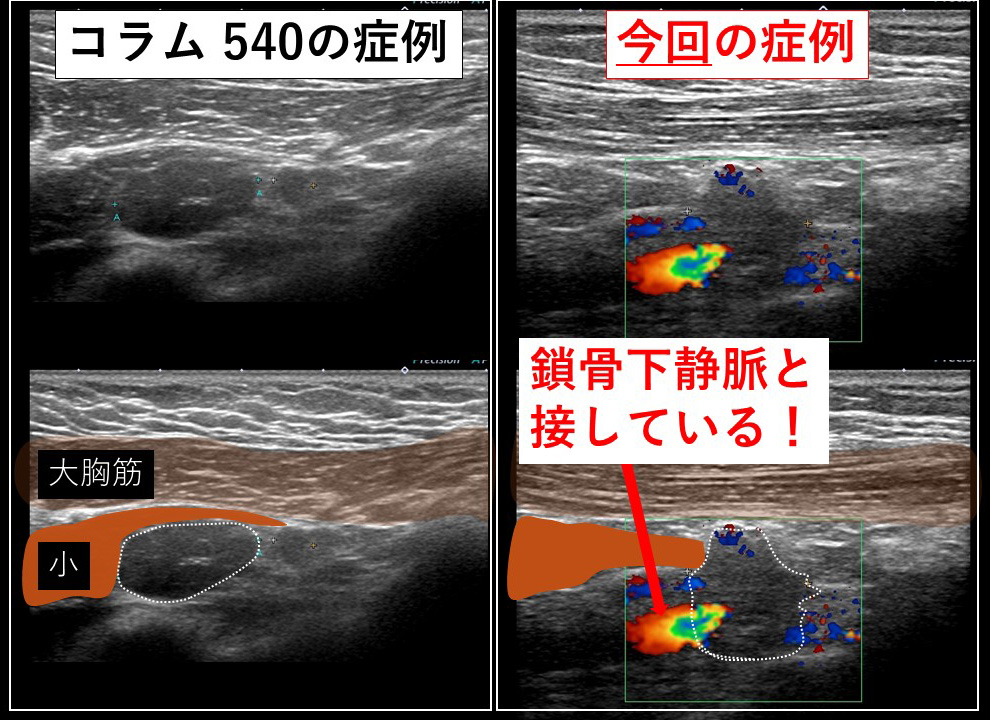

まずは前回のコラム(540回)の症例と対比します。

リンパ節が「節外浸潤」していること。

リンパ節を(エコーで捉えると)どの角度であれ「鎖骨下静脈」が一緒に写ってくること…

向かって左が「コラム540症例」 右が今回の症例となります。

通常の腋窩郭清(小胸筋内縁まで)の視野です。

鎖骨下リンパ節(レベルⅢ)は「小胸筋の向こう(奥)」にあるので『小胸筋を何とかしなくては』そこへはアプローチできません。

手前に引っ張り出せば図左のように鎖骨下リンパ節が「ばっちり」鎖骨下静脈と離れて認識できます。

これ(向かって左の図)が「コラム 540回目症例」であり、それであれば「何てこともない」のですが…

向かって右に見える「今回の症例」は(小胸筋を引っ張っても)節外浸潤した鎖骨下リンパ節が(エコーで想像した通り)鎖骨下静脈に(恋人たちのように)ぴったりと寄り添って離れない!

鎖骨下リンパ節が鎖骨下静脈から外せない。この視野で無理やり剥がそうとすれば…(考えたくもない)